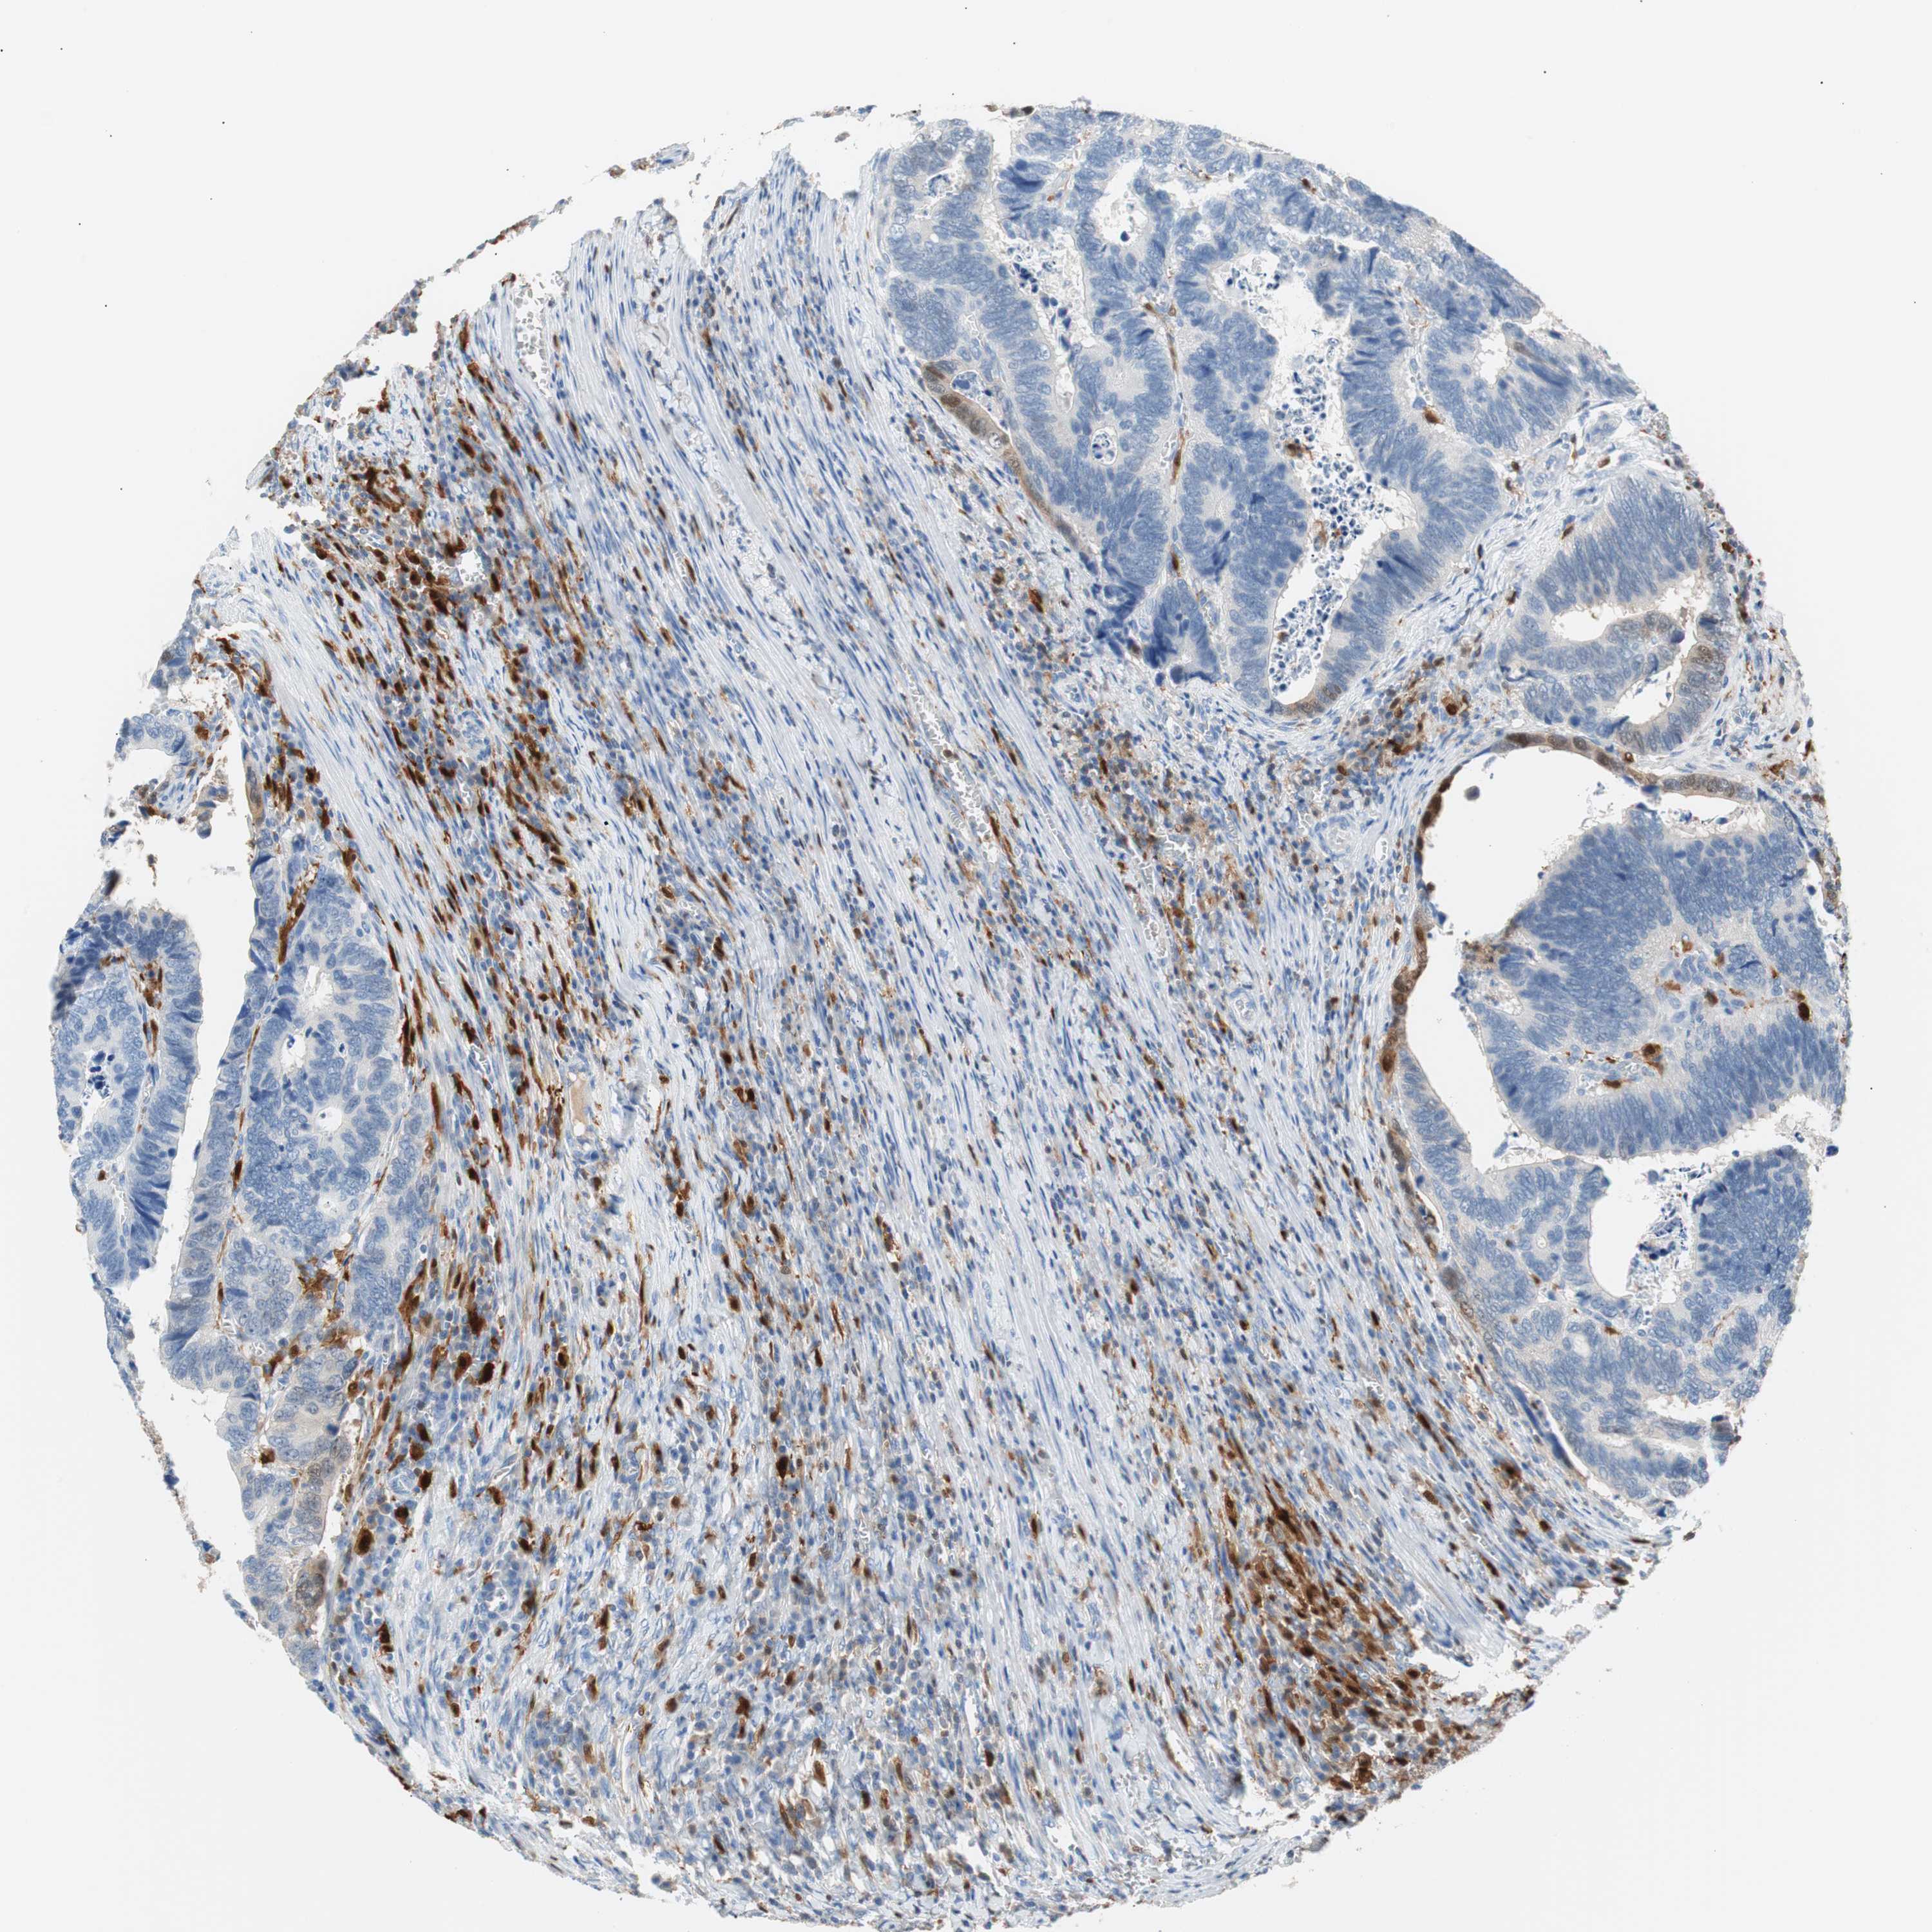

CANCER COLORECTAL CANCER Show tissue menu

Colorectal cancer

Human cancer